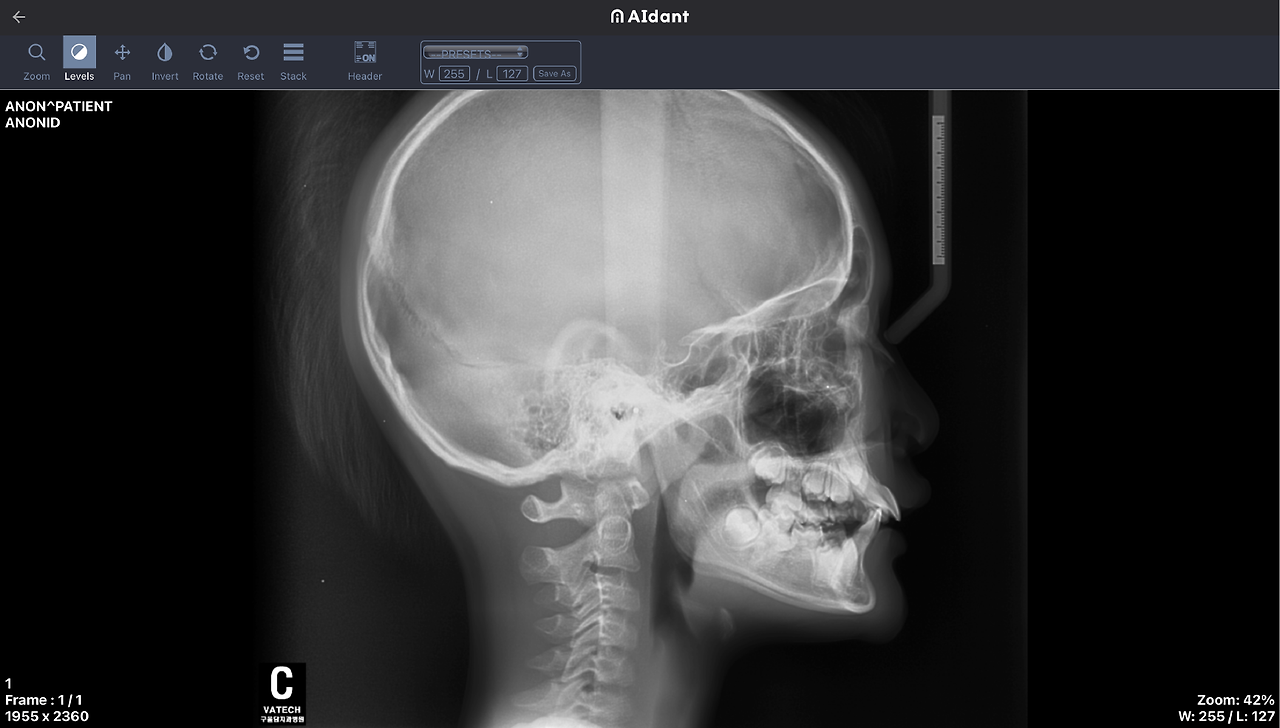

etc_2.png 에이던트 Lateral cephalometry parameter measurement 솔루션 실제 화면

저희 프로메디우스도 이에 발맞추어 인공지능을 활용한 시스템을 개발하고 있습니다. 에이던트의 솔루션 중 치의학 분야에서 주로 사용될 수 있는 Lateral cephalometry parameter measurement으로 예를 들어볼 수 있는데요. 이 솔루션은 측면 두부 X-ray 영상에서 42개의 Landmark를 인공지능으로 자동 검출하고, 부정교합 진단에 필요한 거리지표와 각도지표를 표시해 줍니다. 2023년 1월 기준으로 현재 42개의 Landmark의 위치를 알 수 있으며, 3월부터 위치 정보를 통해 거리지표, 각도지표를 함께 제공받으실 수 있습니다.

그러나 에이던트 Lateral cephalometry parameter measurement 솔루션과 같은 인공지능 솔루션에서는 처음부터 수고스럽게 점을 찍을 필요 없이 단 5초 만에 1.05+/-0.91mm 오차범위 내에서 가이드 포인트를 제공받을 수 있습니다. 그 포인트들로부터 객관적인 지표를 의료인은 얻을 수 있게 되는 거죠. 이는 복잡한 워크플로우를 개선하여 의료 연구의 효율을 높여주고 정확한 의료적 판단을 보조하는 역할을 합니다.

학습에는 총 862장의 Lateral cephalometry X-ray 영상이 사용되었으며, 성능 검증에는 총 100장의 영상이 사용되었습니다. 누구든 회원 가입만 하면 에이던트 AI 솔루션을 의료 연구에 바로 적용해 볼 수 있습니다. 더 자세한 사항과 직접 사용해 보길 원한다면 https://www.aidant.io/ 에서 지금 만나세요!